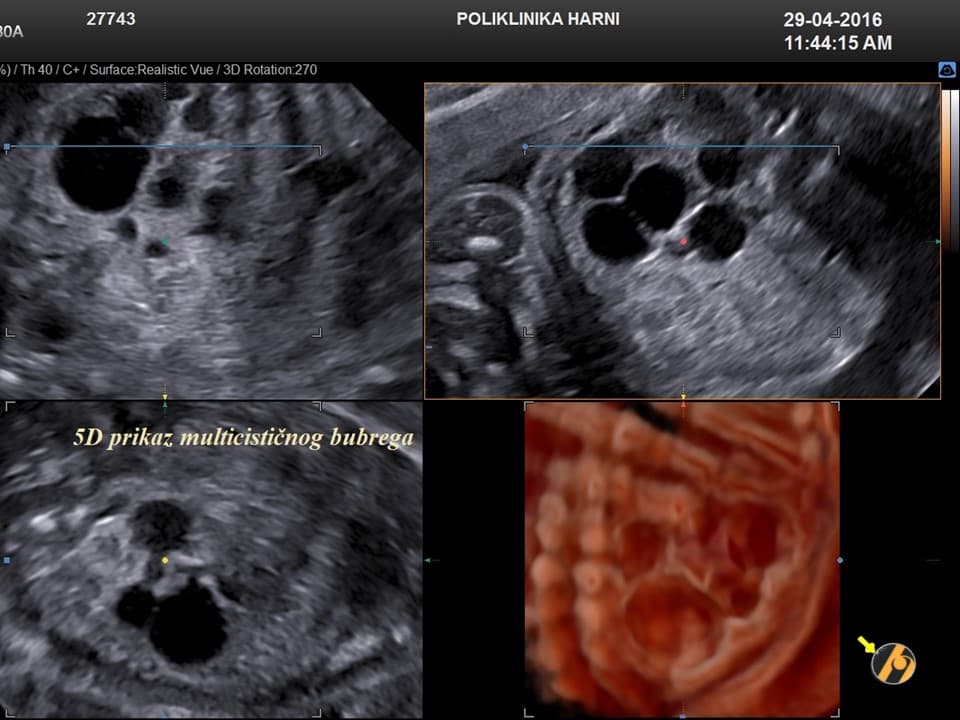

Oko 20. tjedna trudnoće obično se obavlja detaljan ultrazvučni pregled drugog tromjesečja, poznat kao morfološki ultrazvuk ili anomaly scan. Tijekom tog pregleda procjenjuju se razvoj i anatomija fetusa, razvoj mozga, srca i drugih organa, količina plodove vode te položaj i izgled posteljice.

Ovaj pregled omogućuje liječniku da procijeni razvija li se beba uredno te pruža važan uvid u tijek trudnoće, kao i da preporuči dodatne pretrage kao što su fetalna neurosonografija ili fetalna ehokardiografija.